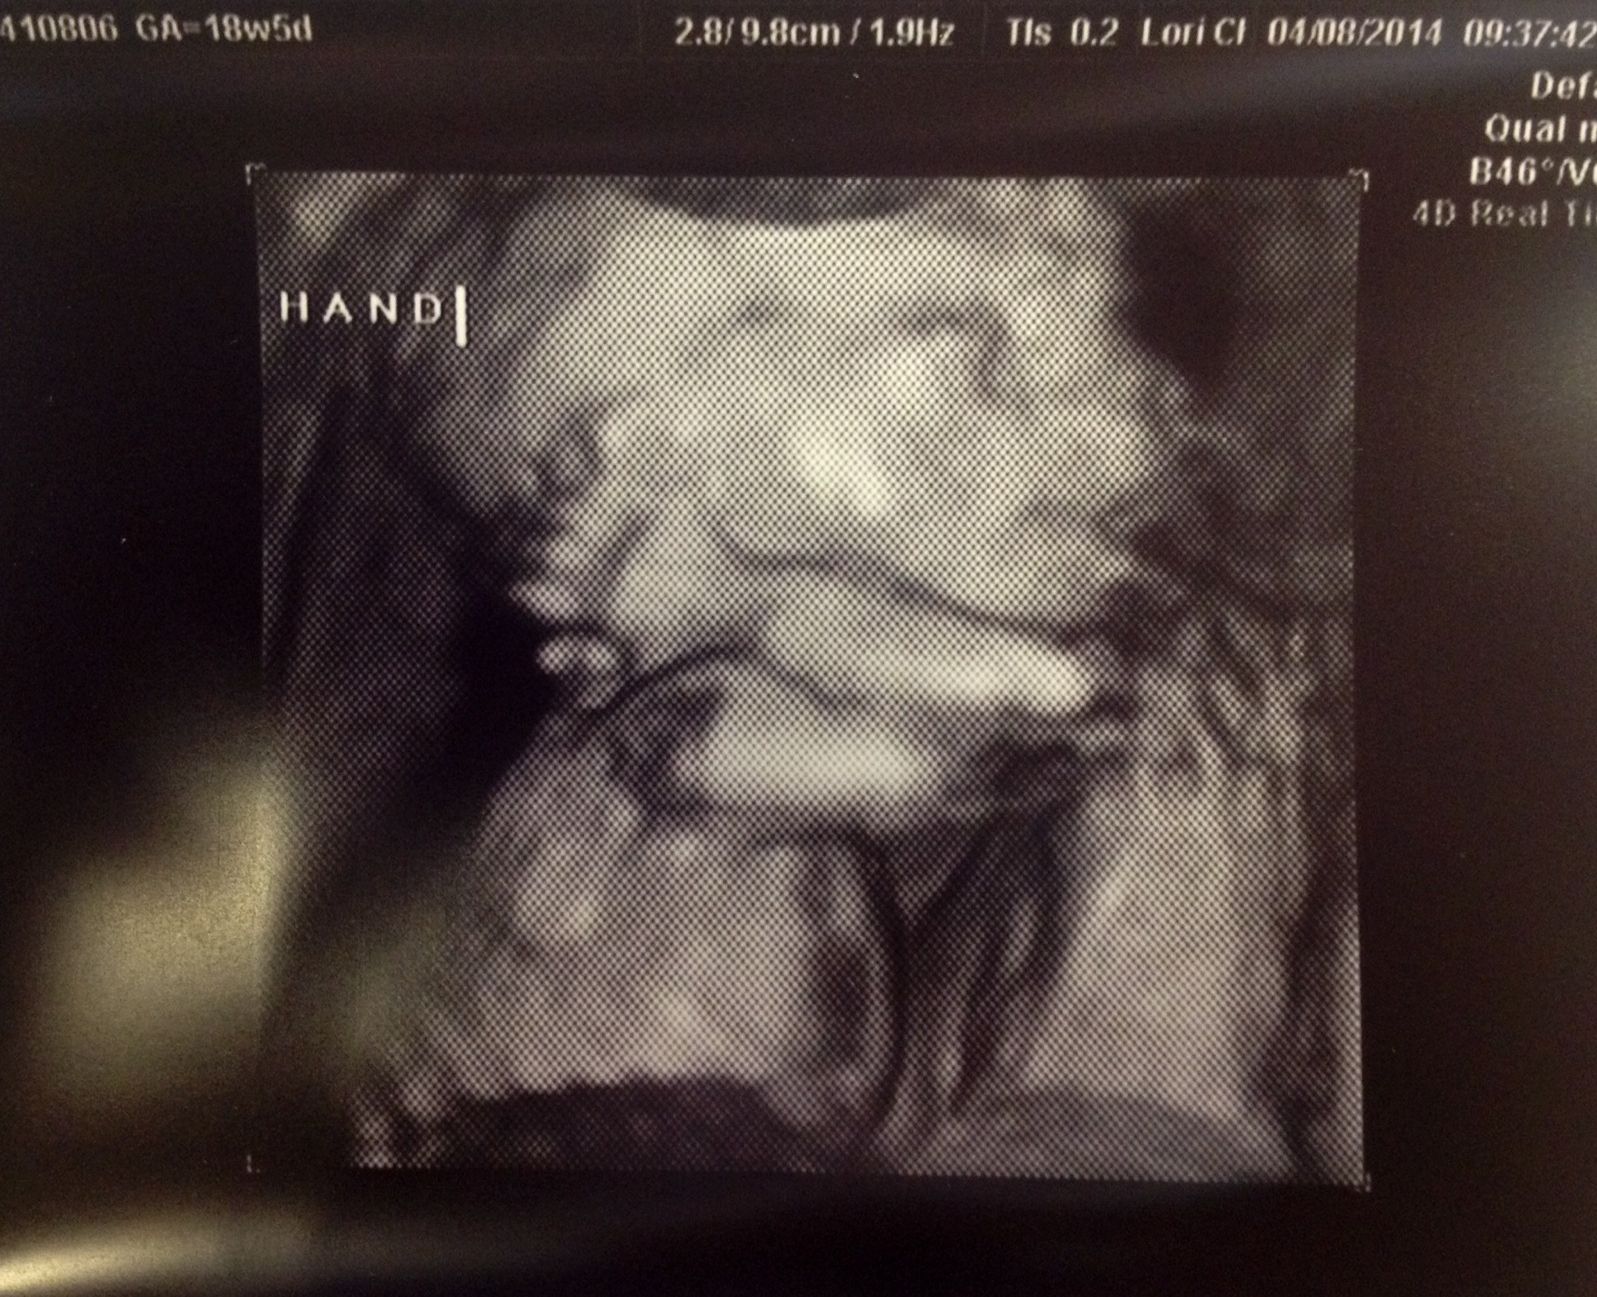

Just wanted to share that we had our anatomy scan today and everything went and looked well. Also, we are TEAM PINK!!

There was a bit of a scheduling problem (meaning that my appointment got erased from their scheduler?) when they merged systems with a larger healthcare provider at the beginning of the month, so to make up for it they showed us some 3D ultrasound shots at no charge! Made my day!!

• Congratulations! I love the 3D shot, very cute!